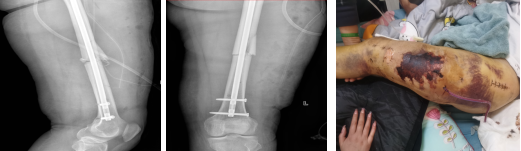

图3、4术前的DR检查

患者和家属了解到有省医院对口支援医师,在认同治疗方案和风险后要求支援医师主持手术。术中,姚豹医生凭借高超的手术技巧和丰富的手术经验,巧妙使用骨科“金手指”器械撬拨闭合复位股骨干骨折,在微创下达到了解剖复位有效减少了手术创伤、后期护理难度和患者痛苦,微创下手术复位成功。

图5、6手术治疗

图7、8术后复查DR 图9术后换药治疗